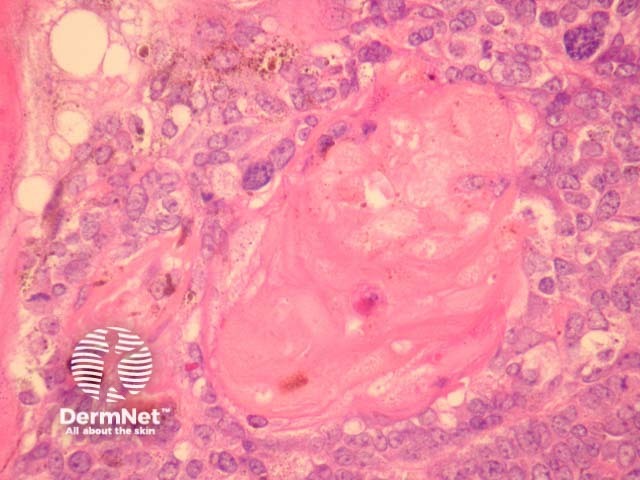

Sections through melanocytic matricoma show a well-circumscribed dermal tumour which may encroach and erode the overlying epidermis (figure 1). There is heavy melanin deposition. The tumour is made up of basaloid cells with some nuclear pleomorphism and conspicuous mitotic activity. Intermixed with these epithelial cells are a population of dendritic melanocytes (figures 1-4). There is focal “ghost cell” keratinisation (figures 5, 6).

Figure 4